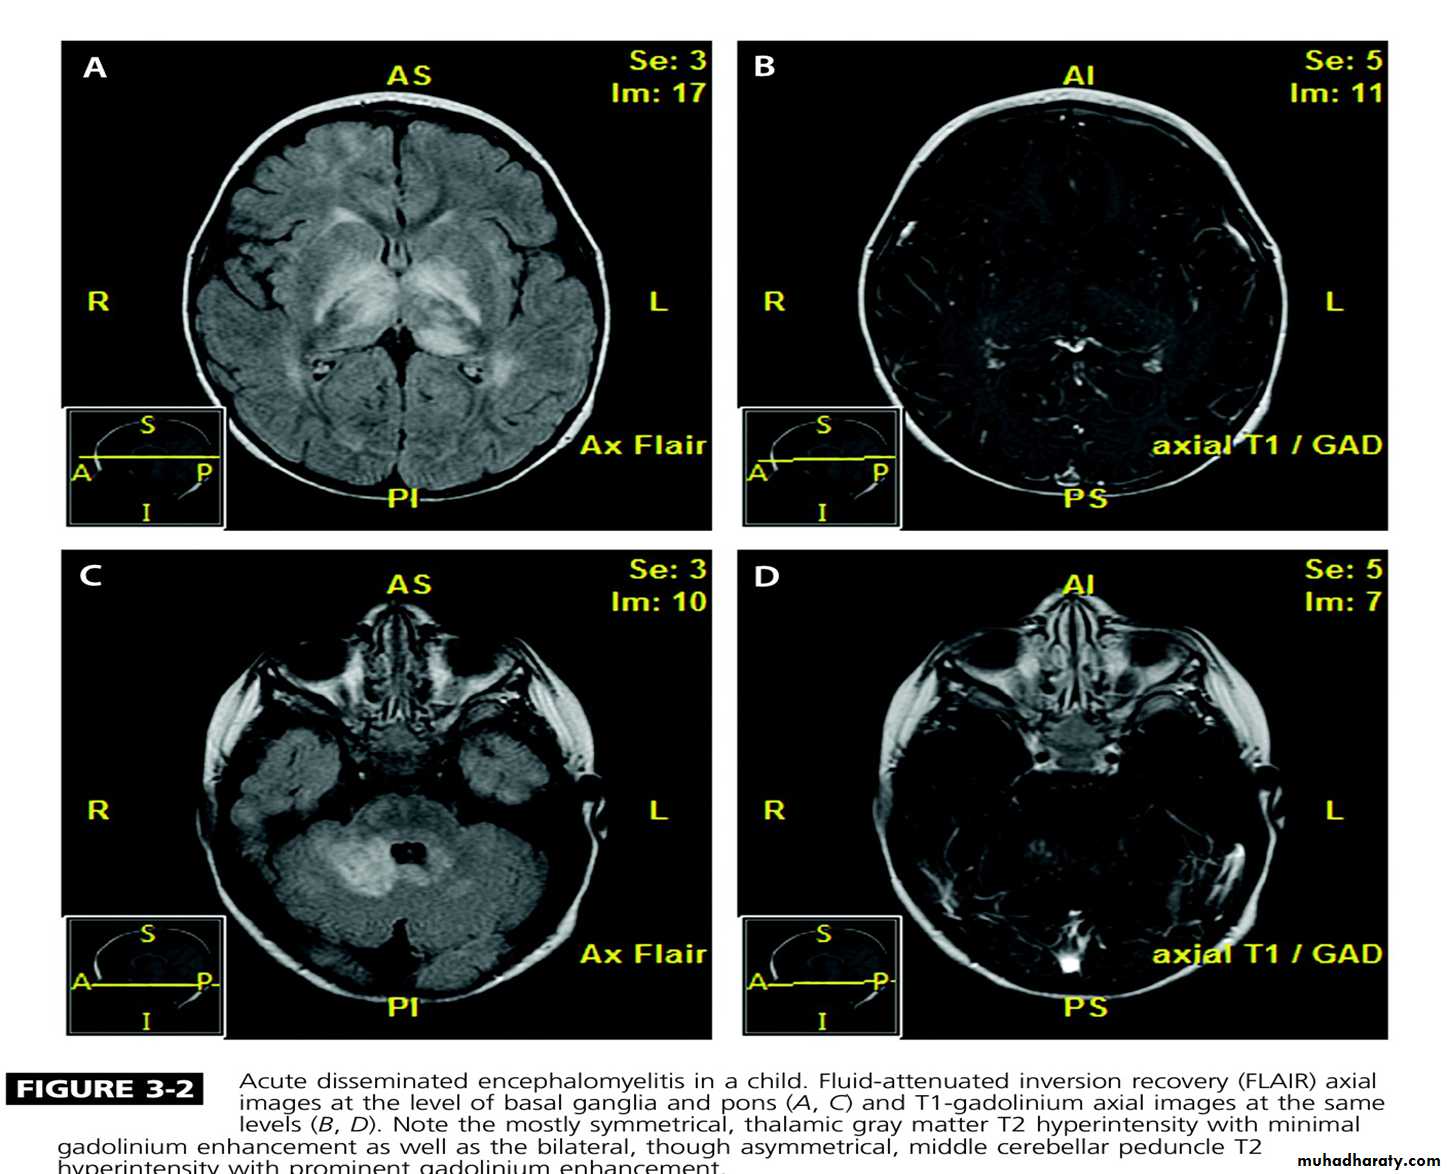

Acute disseminated encephalomyelitis

This is an acute monophasic demyelinating condition in which there are areas of perivenous demyelination widely disseminated throughout the brain and spinal cord. The illness may apparently arise spontaneously but often occurs a week or so after a viral infection, especially measles and chickenpox, or following vaccination, suggesting that it is immunologically mediated.

Clinical features:

Headache, vomiting, pyrexia, confusion and meningism may be presenting features, often with focal or multi focal brain and spinal cord signs. Seizures or coma may occur.

A minority of patients who recover have further episodes mainly in children.

Investigations:

MRI shows multiple high-signal areas in a pattern similar to that of MS, although often with large confluent areas of abnormality. The CSF may be normal or show an increase in protein and lymphocytes (usually 200 cells/L) . The clinical picture may be very similar to a first relapse of MS.

Management:

The disease may be fatal in the acute stages but is other wise self-limiting. Treatment with high-dose intra venous methylprednisolone, using the same regimen as for a relapse of MS, is recommended.